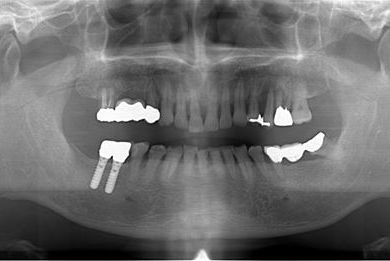

インプラントの症例写真 IMPLANT

抜歯即日スピードインプラント治療

| 治療方針 | 抜歯と同時にインプラント埋入を行い、治療期間を短縮する。 | ||||||||||||||||||||||||||||||||

| 治療内容 | インプラント2本(抜歯即日スピードインプラント) | ||||||||||||||||||||||||||||||||

| 治療期間 | 10ヶ月 |